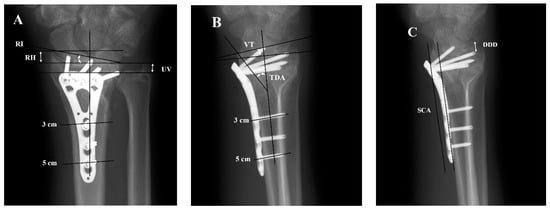

2.2. Analysis of Forearm X-ray Images

- Paired t-tests and Wilcoxon signed-rank tests were used to compare radial height (RH), ulnar variance (UV), radial inclination (RI), volar tilt (VT), teardrop angle (TDA), and distal dorsal cortical distance (DDD) immediately after the operation and 3 months following the operation within each of the two groups.

- Student’s t-tests were used to compare RH, UV, RI, VT, TDA, and DDD immediately after the operation with 3-months follow-up in the extra-articular and intra-articular groups, as well as to compare the 3-month change in RH, UV, RI, VT, TDA, and DDD between these two groups.